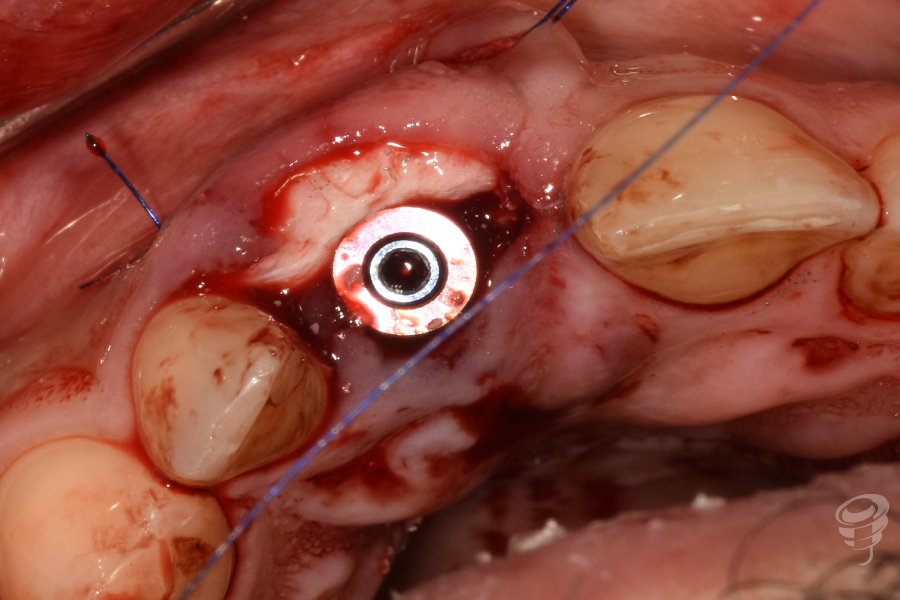

- Injerto óseo: Colocación de partículas xenogénicas y de fresado propio en el gap vestibular y coronal al implante. Injerto de tejido conectivo: Obtenido de la tuberosidad. Injerto subepitelial tunelizado vestibularmente al implante y suturado con Seralene 5-0.

Figura 15

- Provisionalización: Pilar titanio personalizado + corona provisional de resina acrílica (sin contacto oclusal), con la colocación de puntos suspensores para estabilizar la encía y márgenes gingivales.